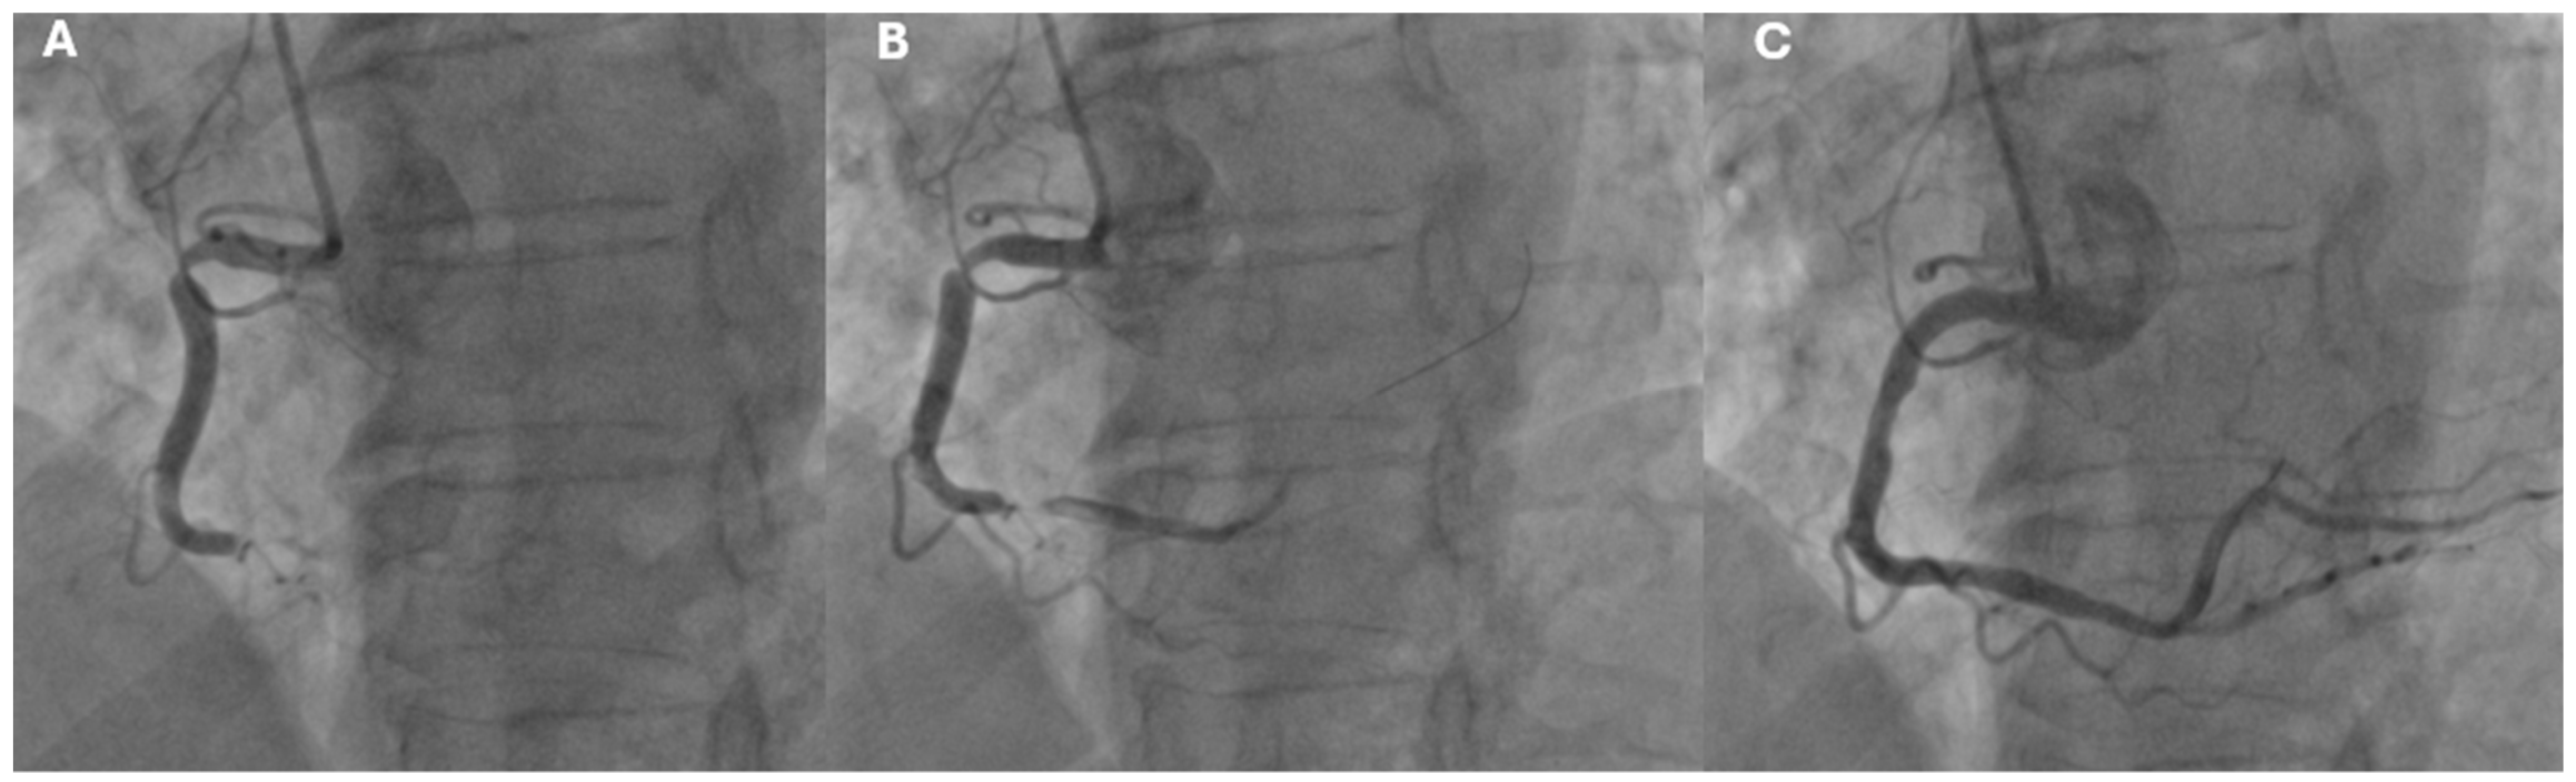

- STEMI (ST-Segment Elevation Myocardial Infarction): Defined by persistent ST-segment elevation on the ECG, typically indicating complete blockage of a coronary artery (Figure 2).

4.1. Treatment of Acute Coronary Syndrome